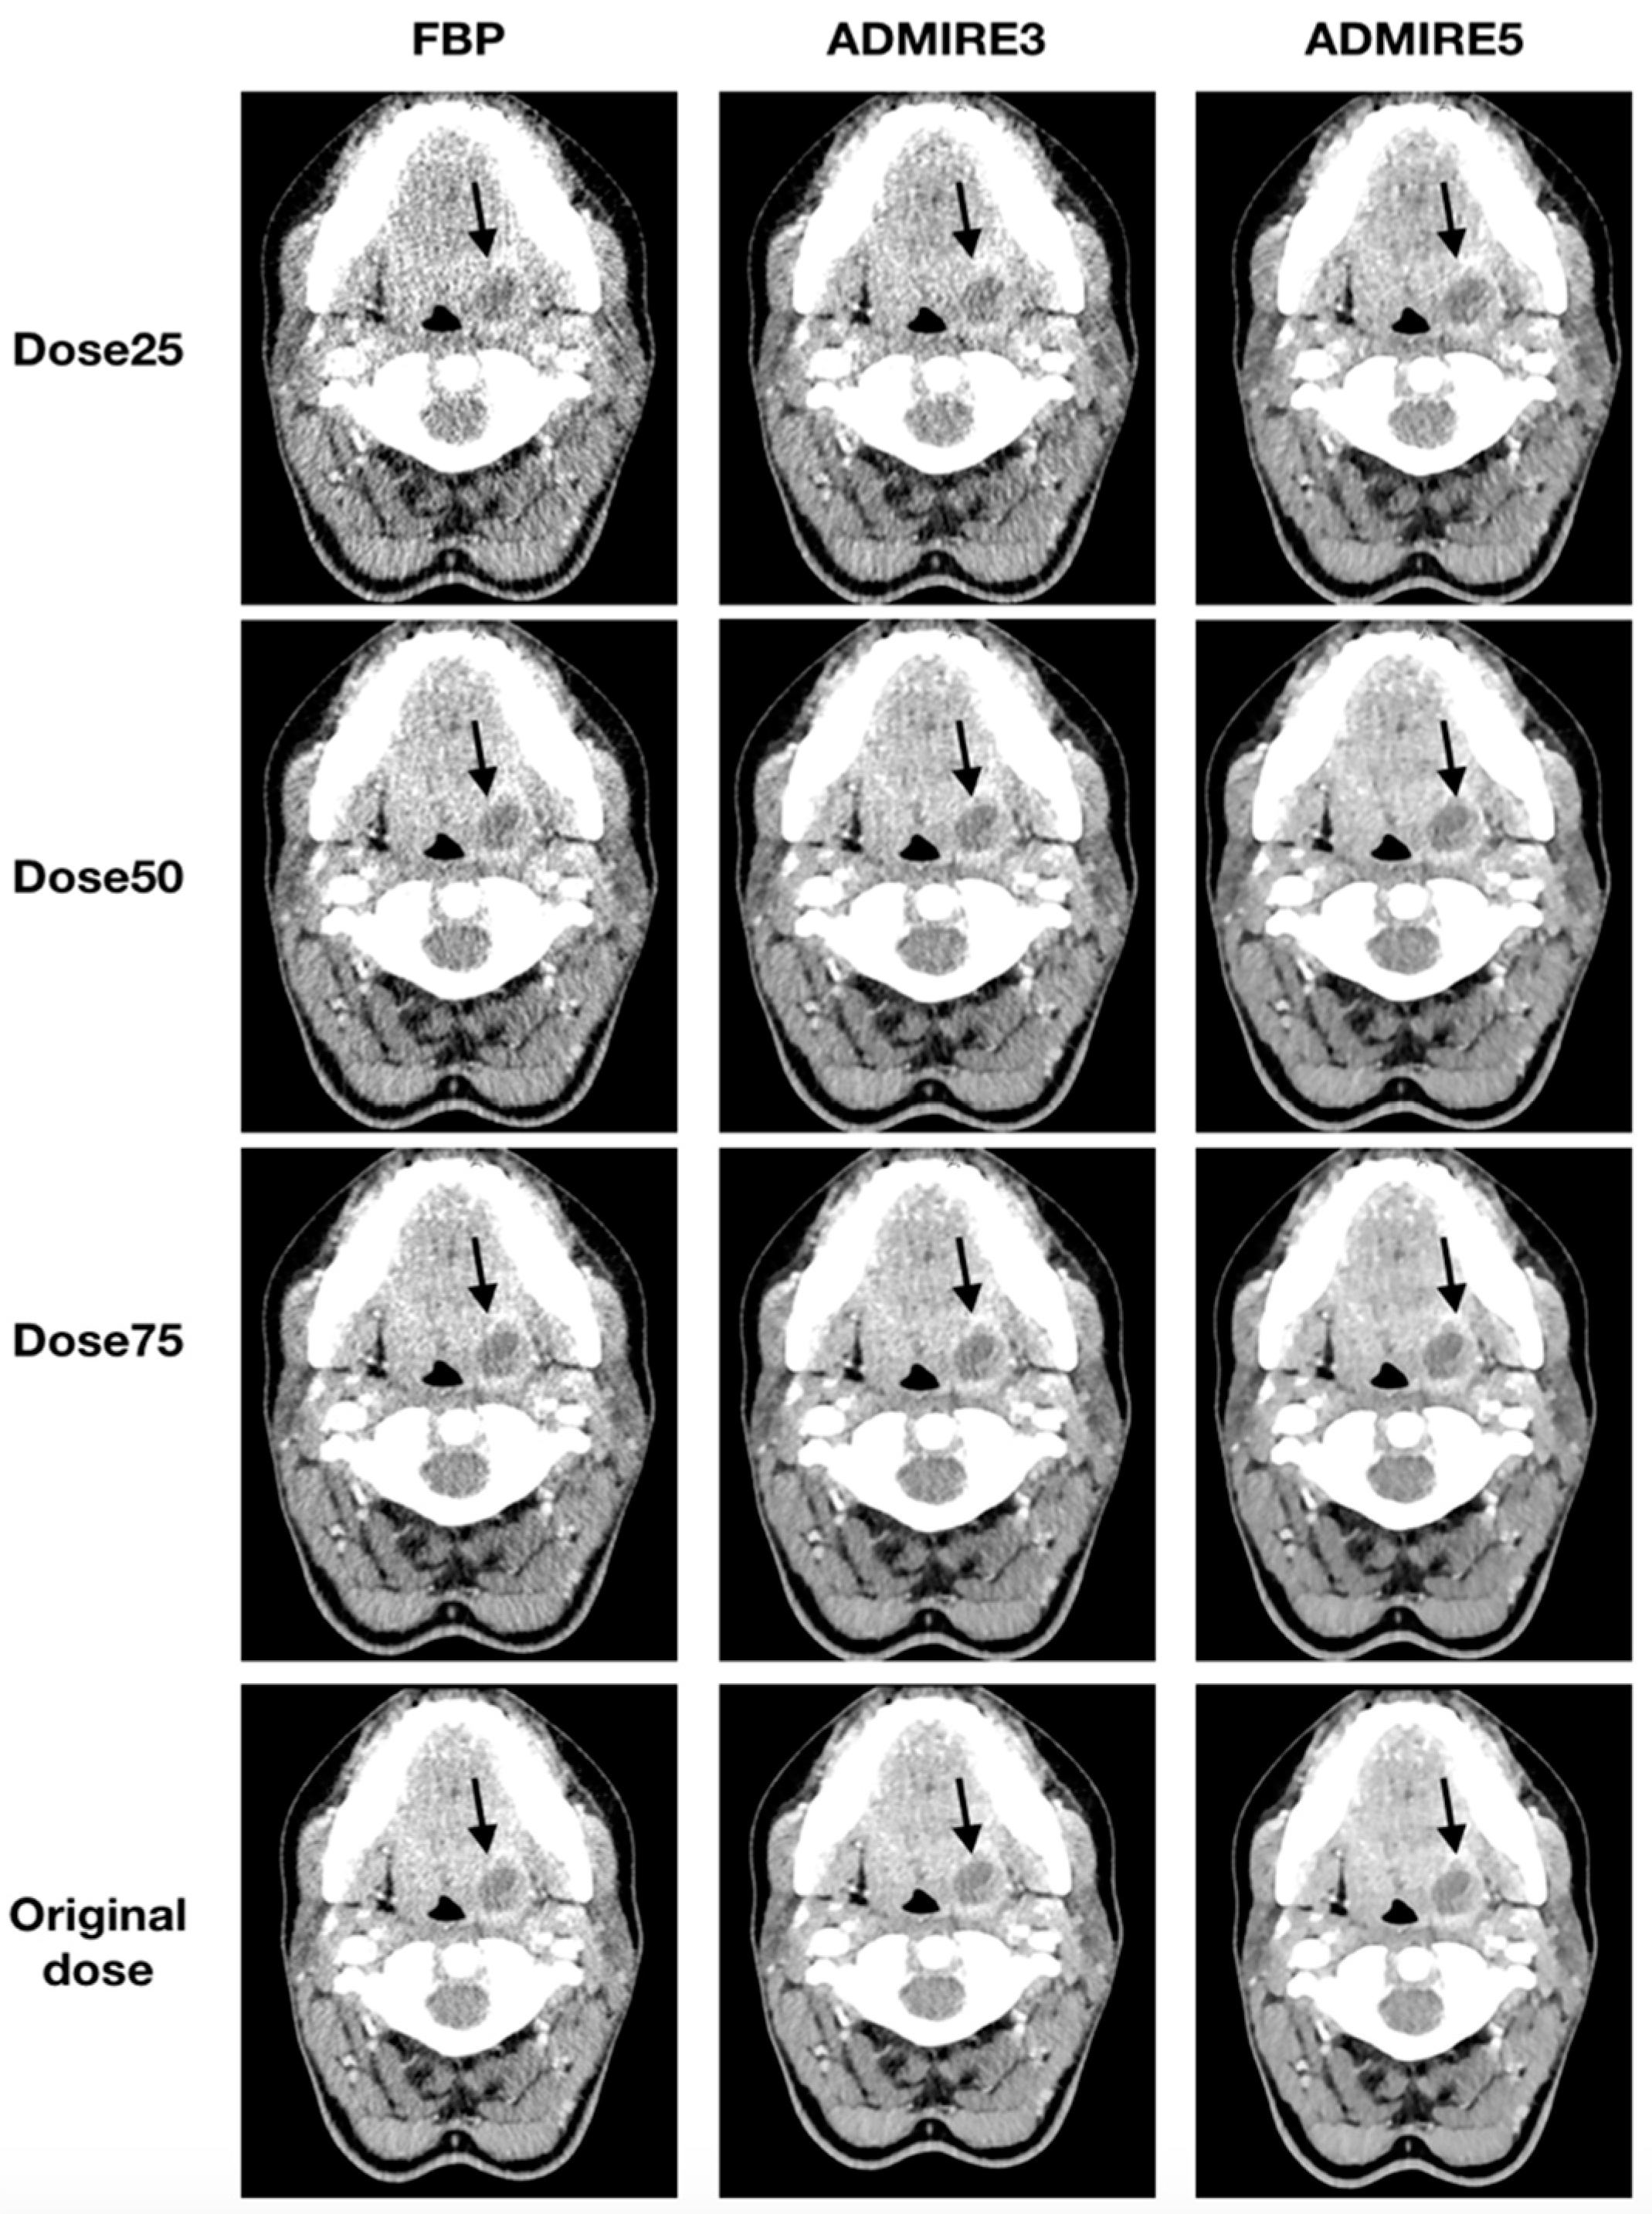

All 48 patients were analyzed for the presence of a neck abscess. A total of 35 abscesses were diagnosed in the original datasets. All three blinded readers had a sensitivity of 100% (95% CI: 88–100) and specificity of 100% (95% CI: 72–100) for all simulated low-dose datasets, which were iteratively reconstructed with ADMIRE 3 or ADMIRE 5. FBP datasets had a sensitivity of 100% (95% CI: 88–100) and a specificity of 100% (95% CI: 72–100) for a dose reduction to 50% of the original dose. Deviations were only found in FBP reconstructed datasets at a dose of 25% of the original dose. Illustrations of the different reconstructions at the respective dose levels are shown in Figure 5 and Figure 6.

Figure 5.

Axial tomographic slices of an 18 year old female patient with left-sided peritonsillar abscess (arrow). The images were reconstructed with FBP, ADMIRE 3, and ADMIRE 5 (from left to right) at 75%, 50%, and 25% dose reduction of the original dose.